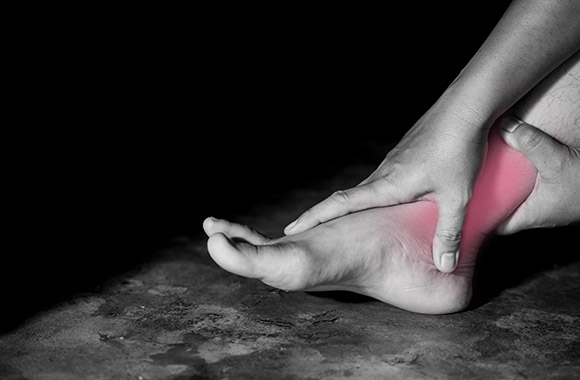

Plantar fasciitis

Description:

The plantar fascia is a strong ligament that runs along the sole of the foot and when overloaded it can cause heel pain.

Treatment:

Non-operative treatments include anti-inflammatories, soft insoles, injections and physiotherapy. In rare instances it may require surgery that is usually performed in the calf muscles to offload the tension they put on the plantar fascia.